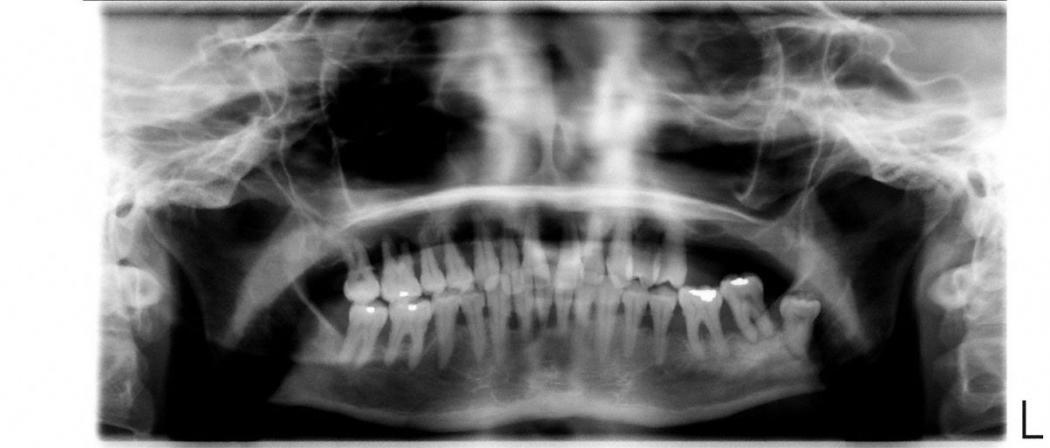

Eine initiale Diagnostik kann eine Fotodokumentation, die Erstellung diverser Indizes (z. B. Plaqueindex, API) und Röntgenaufnahmen beinhalten. Bei den Röntgenaufnahmen wird eine Panoramaaufnahme angefertigt. Von nicht vital reagierenden und wurzelgefüllten sowie nicht auf der Aufnahme ausreichend erkennbaren Zähnen werden Zahnfilme erstellt. Die Röntgendiagnostik gibt Auskunft über Zustand, Form und Beschaffenheit von Zahnhartsubstanz, Alveolenknochen, Desmodontalspalt und Restaurationen.

Vor Beginn einer Parodontalbehandlung ist eine Befunderhebung des Zahnhalteapparates (Parodontium) nötig. Da die radiologische Bewertung eher einen überprüfenden Charakter hat, sind die Sondierungswerte und die Beurteilung des Parodontiums sichere Parameter für die Diagnostik.